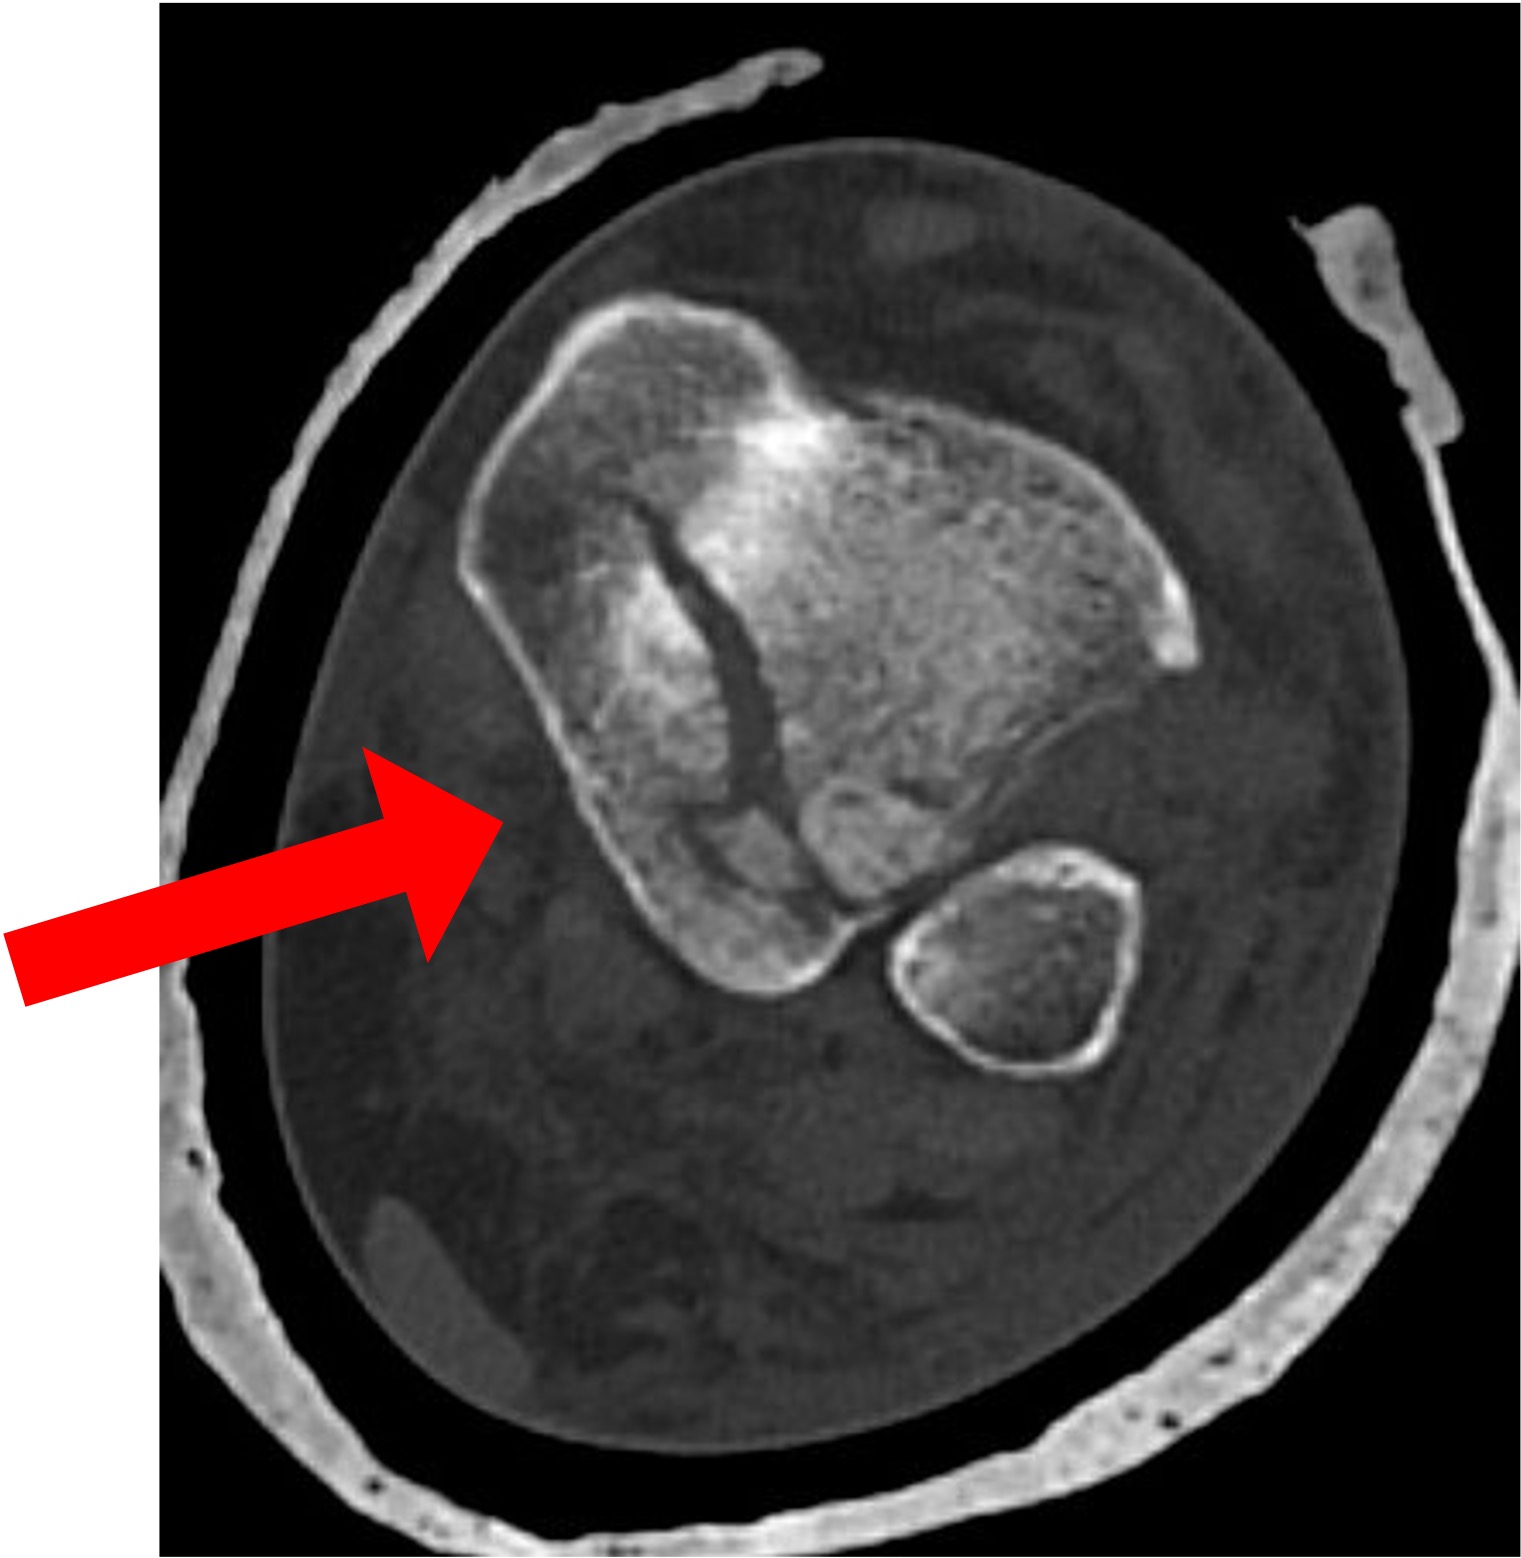

CT scan is the preferred test:

- Fracture configuration

- ‘Die-punch’ fragments

- Intra-articular fragments

Figure 1: Mason & Molloy (2017)